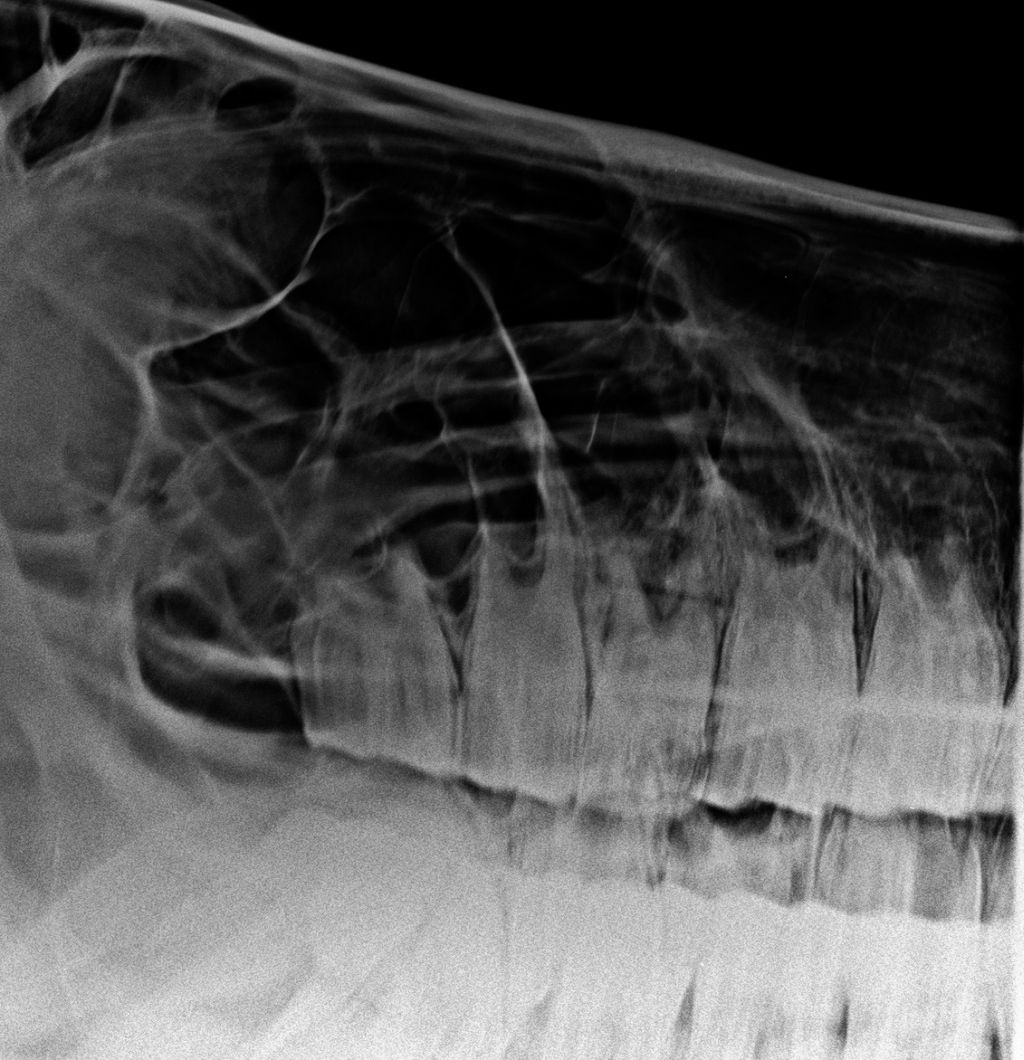

Sie machen einen Termin, ich schicke die Vorgeschichte an die Klinik und die Nachbehandlung übernehme anschließend ich oder der Haustierarzt/ die Haustierärztin. - Die Extraktion kann im Stall durchgeführt werden. Wir machen ggf. Röntgenbilder, besprechen die Vorgehensweise und im Idealfall lässts sich der Zahn dann wie geplant ziehen.